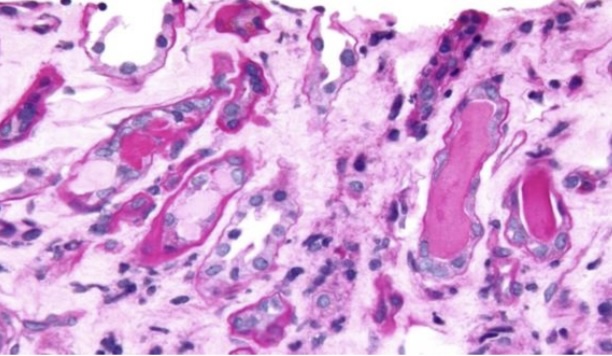

Ballooning degeneration

Hydrophic degeneration

Cell swelling